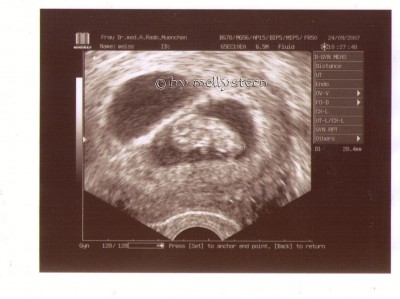

SST positiv! -> das herzchen schlägt!